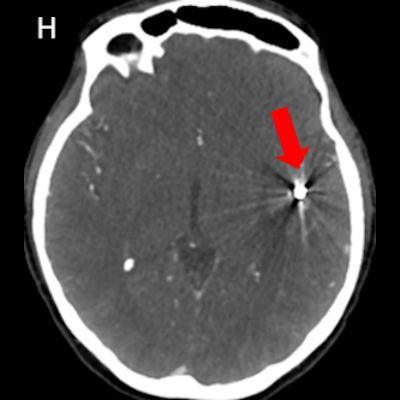

- DSA görüntülemede (G) sol MCA M2 segmentinde anevrizmatik dolum fazlalığı izleniyor (ok). Bu anevrizmaya eş zamanlı koil işlemi yapılıyor (oklar) ve işlem sonrası kontrol BT anjiografi görüntüsünde (H) metalik koil materyali izleniyor (ok).